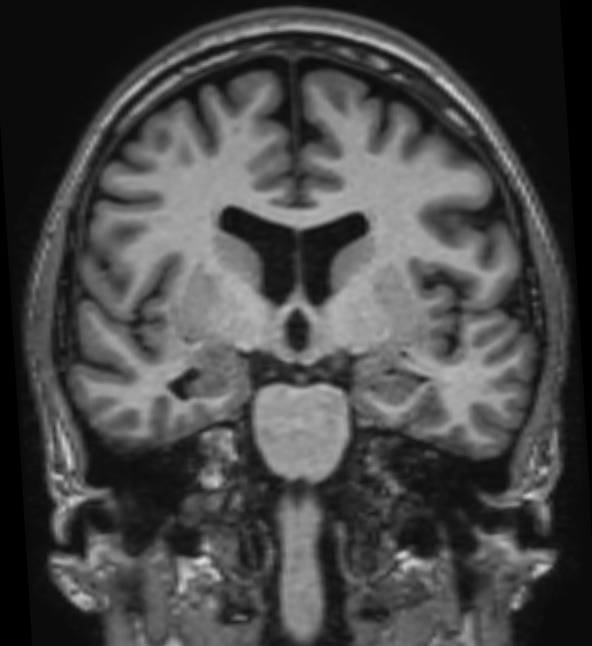

МРТ гиппокампов

Магнитно-резонансная томография гиппокампов – важный метод исследования, который позволяет оценить состояние гиппокампов.